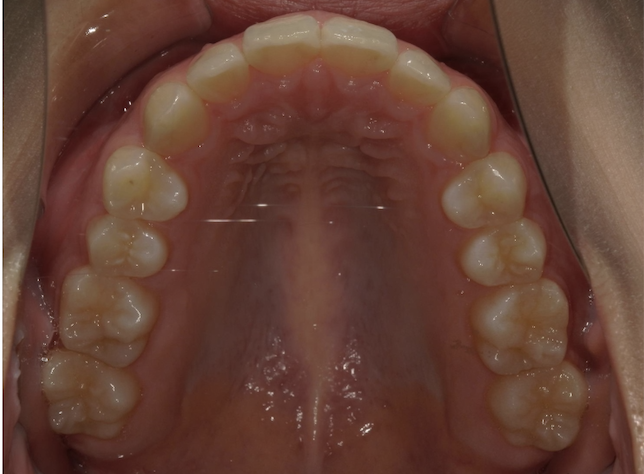

マウスピース矯正やワイヤー矯正に加え、必要に応じてアンカースクリューを活用することで、より複雑で難しい歯並びの症例にも対応しています。これにより、従来の矯正だけでは難しかった歯の移動も可能となり、幅広い治療の選択肢をご提供できます。

当院では、マウスピース型矯正装置を院内で設計・制作する「インハウスアライナー」を導入しています。

外部発注が不要なため、型取り後すぐに矯正治療を開始でき、費用も抑えられます。

院内完結だからこそ、患者様の歯の状態に合わせた細やかな調整ができ、スムーズで短期間の治療を実現します。

症例

矯正歯科専門の歯科医師が専門的な知識と確かな実績を

もとに患者様にあった最適な治療プランをご提案します。